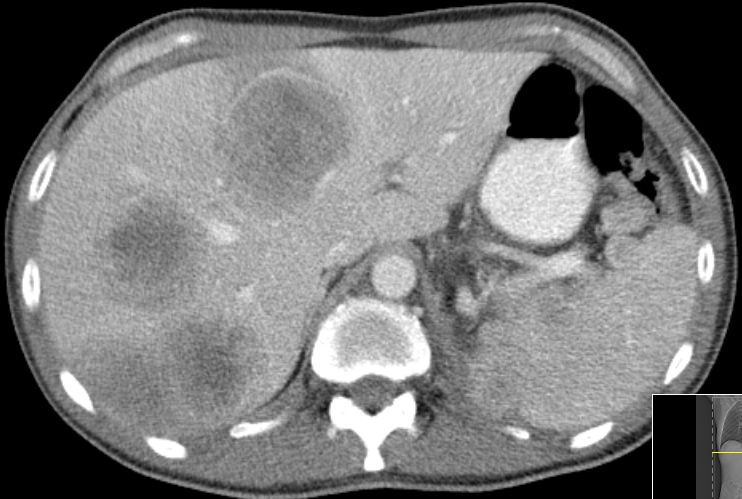

52-jähriger Mann mit klarzelligem

Nierenzellkarzinom mit sarkomatoider Entartung. In der Leber große

Metastasen.![]() |